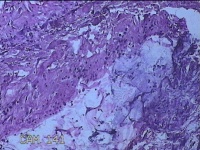

左侧腋下结节

性别

女

年龄

22岁

临床诊断

皮下结节;皮脂腺囊肿

一般病史

发现左侧腋下结节伴隐痛不适1周余。

标本名称

大体所见

灰白暗红色带皮肤样结节2.5x1.5x0.7cm一个,表面糜烂,切开结节呈实性,切面灰白淡黄色,质软。

图1